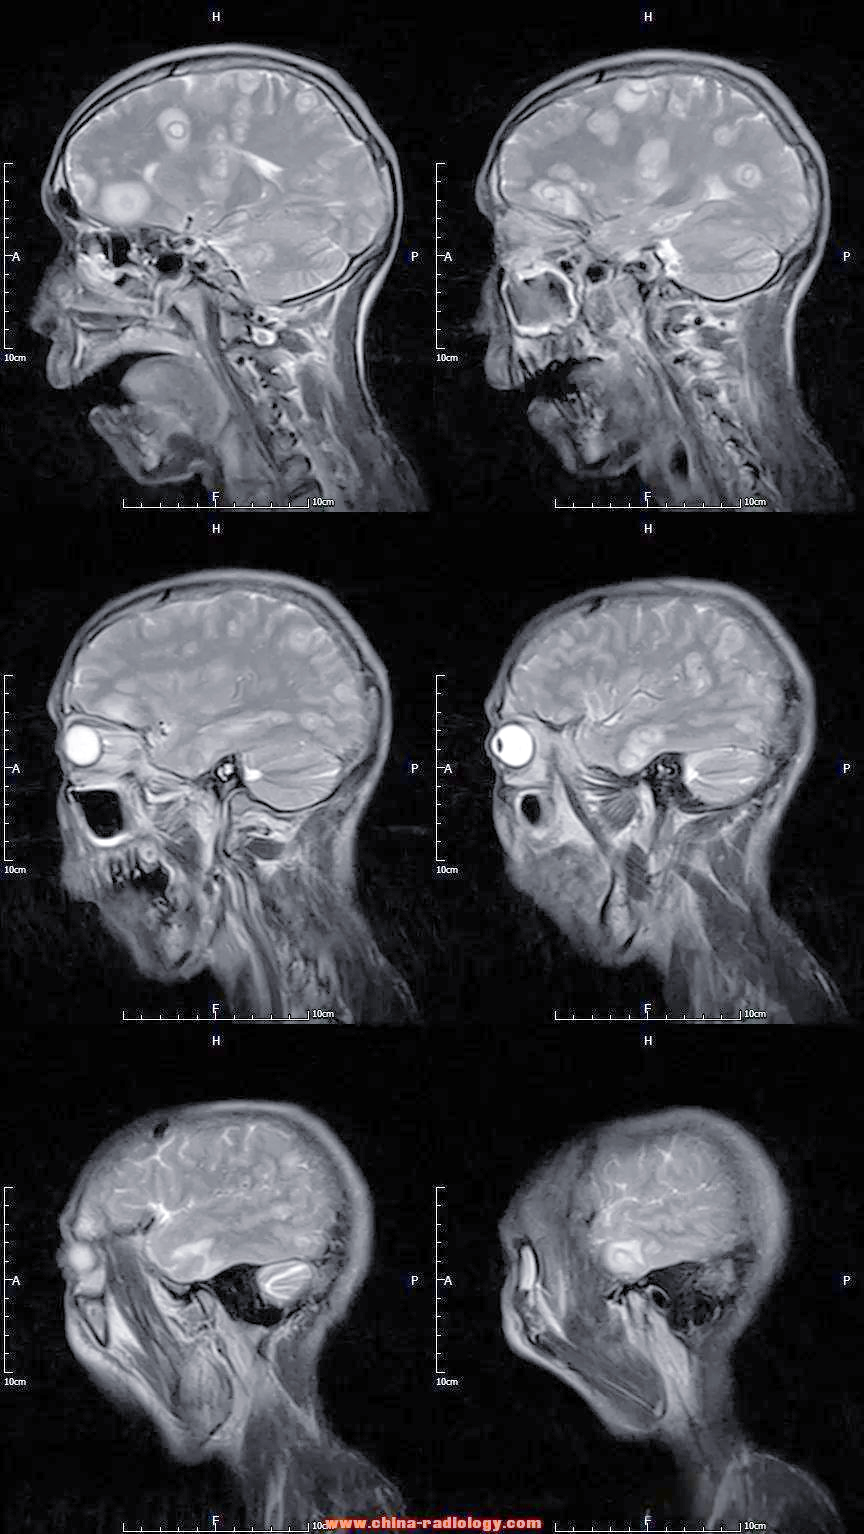

脑囊虫病

术语缩写脑囊虫病(neurocysticercosis,ncc)同义词囊虫病定义由猪肉

囊虫病:一种常见的中枢神经系统寄生虫感染